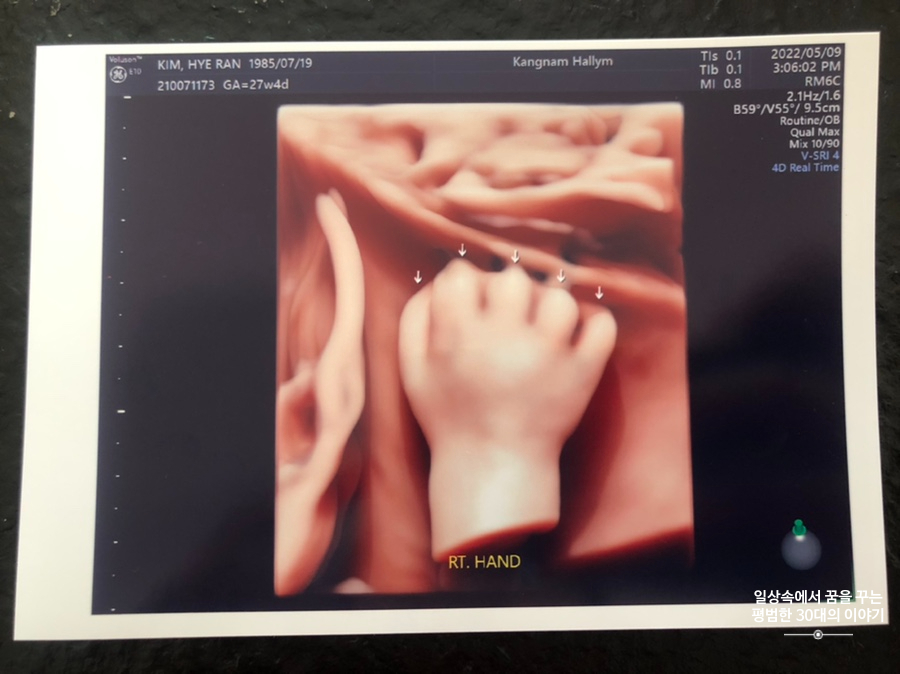

오늘은 입체 초음파 보는 날!!! 입체 초음파는 처음인데다 3주 만에 이안이 얼굴을 본다 생각하니 무척 설레는 마음으로 병원에 갔다. 첫 번째 시도에서는 계속 내 등 쪽으로 얼굴을 대고 엎드려 있어 실패! 초코우유 먹고 열심히 걸은 후, 30분 뒤에 다시 진행한 두 번째 시도에서는 얼굴 반쪽을 보여줬다. 얼굴 전면을 보지 못해 너무 아쉬웠지만 그래도 손가락 빨고 있는 모습, 웃고 있는 모습, 입 뻐끔 거리는 모습, 발차기 하는 모습, 손가락 쥐었다 폈다 하는 모습, 손을 휘적휘적 거리는 모습 등 다양한 모습을 보여줘서 그것만으로도 충분히 만족스러웠다. 내가 다니고 있는 강남성심병원은 입체 초음파가 다른 병원에 비해 무척 비싼 편인데(진료비 내역을 보니 초음파 진단료가 129800원 나옴) 그나마 위안을 삼을 수 있는 것은 화질이 그나마 좋은 편이라는 것이다.